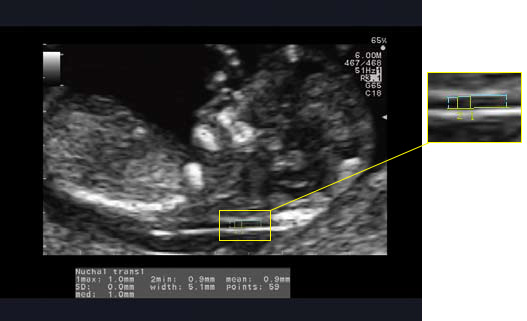

Zautomatyzowany pomiar NT automatycznie wykrywa maksymalne i minimalne NT poprzez ustawienie obszaru zainteresowania (ROI) na tylnej części szyi płodu. Wystarczy, że zaznaczą Państwo odpowiedni fragment a zautomatyzowany pomiar NT automatycznie śledzi i mierzy maksymalną grubość przezierności karkowej.

Funkcja ta jest łatwa, szybka i skuteczna. Najistotniejsze jednak, że minimalizuje różnice w wynikach badania między różnymi operatorami. To z kolei pozwala na większą pewność w ocenie przezierności karkowej.